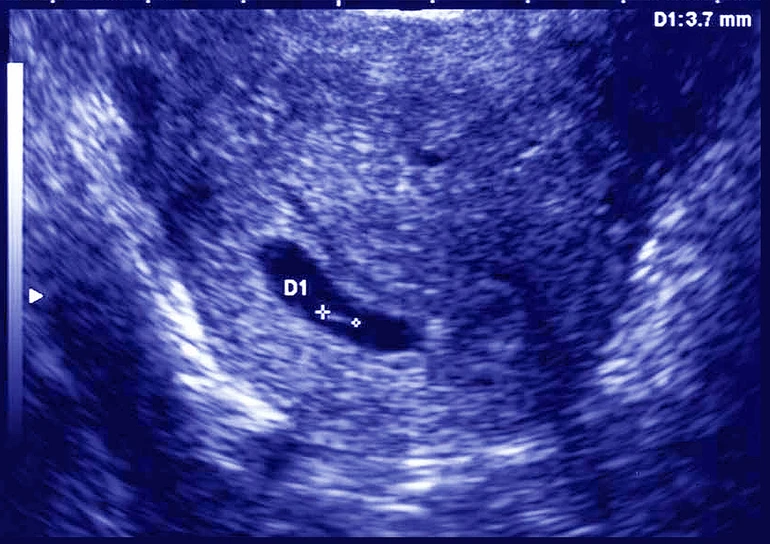

– Залишають обидва. Буває, що після перенесення двох ембріонів ми бачимо два плідні яйця на УЗД. Та за кілька тижнів на повторному обстеженні виявляється, що лишився тільки один. Тобто другий зупинився у розвитку. Тому два ембріони не завжди означають дві народжені дитини.